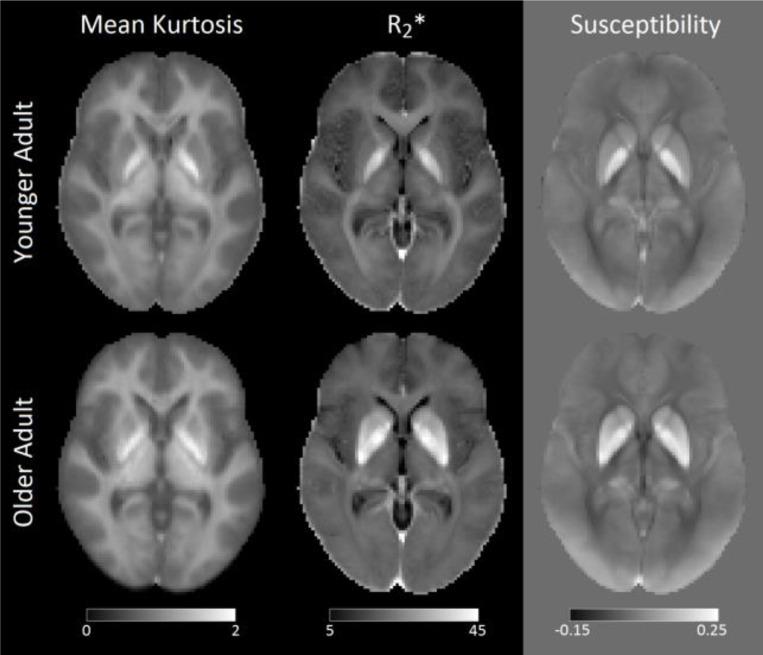

Associations between iron and mean kurtosis in iron-rich grey matter nuclei in aging.

Mean kurtosis in iron-rich grey matter has values similar to that seen in white matter. We suspect these elevated values may be related to iron. Multi-shell diffusion and multi-echo gradient echo acquisitions were used to derive mean kurtosis and R*, respectively. Mean kurtosis and R* were measured in subcortical grey matter nuclei and white matter tracts in 93 older adults and 62 younger adults. Grey matter regions exhibited higher mean kurtosis and R* in the older adult group whereas white matter regions had reduced mean kurtosis in the older adult group. Grey matter mean kurtosis was significantly correlated with R* iron-rich grey matter nuclei in both groups. Our findings indicate that higher mean kurtosis in iron-rich grey matter structures may be due to either increased tissue complexity or to decreases in signal-to-noise ratios from iron deposition.